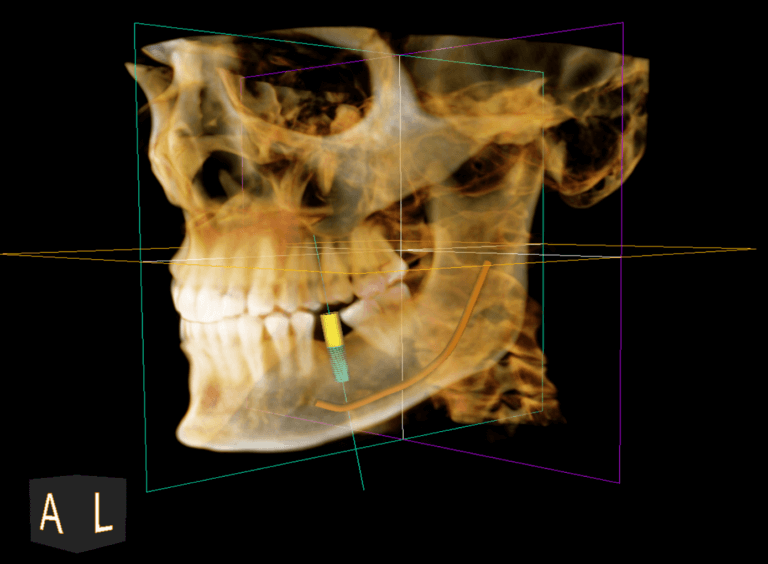

Tomografia computerizată CBCT

Tomografia computerizată (CBCT) oferă medicului o reprezentare tridimensională precisă, la scară reală, a dinților, maxilarelor, sinusurilor și articulațiilor din zona maxilo-facială. Aceasta permite evaluarea volumului și densității osoase, măsurători exacte ale crestei alveolare, precum și identificarea fracturilor, tumorilor, traiectului nervilor, anomalii ale sinusurilor sau afecțiuni ale articulațiilor temporo-mandibulare. Dincolo de rolul său esențial în diagnosticare, tomografia computerizată este crucială pentru planificarea tratamentelor chirurgicale, implanturilor dentare, intervențiilor ortodontice și lucrărilor protetice, contribuind la un plan de tratament mai precis și cu un prognostic optim pentru pacient.